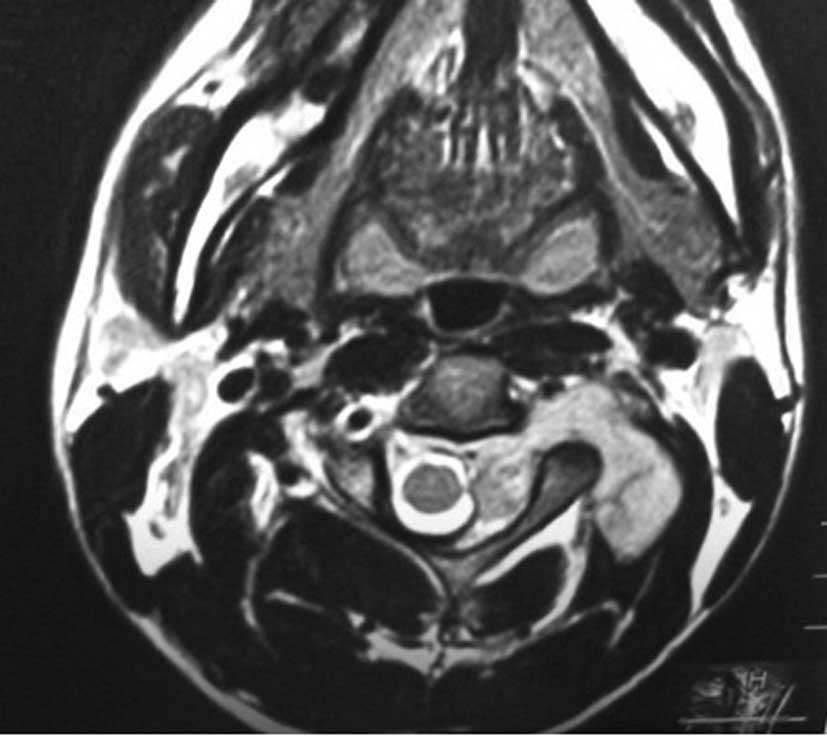

Primary dumbbell-shaped Ewing's sarcoma of the cervical vertebra in adults: Four case reports and literature review

Ewing's sarcoma is the second most common malignant bone tumor in children and adolescents. The 4 cases described in this study were diagnosed with dumbbell-shaped intraspinal and extraspinal Ewing's sarcomas. The incidence of dumbbell-shaped tumors of this type in the spine is 17.5%. These tumors are often misdiagnosed as neurogenic tumors (schwannoma, neurofibromatosis) or giant cell tumors based on imaging. Radiculopathy is more common than spinal cord compression in Ewing's sarcoma. Preoperative biopsy is strongly recommended. As soon as Ewing's sarcoma is diagnosed by pathology, the treatment should begin with 2-3 cycles of neoadjuvant chemotherapy. Anterior-posterior and posterolateral approaches are both recommended for exposing this tumor. Following surgery, chemotherapy is critical to lessen the rate of recurrence and metastasis and to prolong the survival time. However, radiotherapy should be used with caution, as the spinal cord is sensitive to radiation; local irradiation is suggested. The tumor is difficult to remove en bloc in the cervical spine. It has a high rate of recurrence and metastasis. Therefore, the prognosis of Ewing's sarcoma in the cervical region is poorer compared to that in the thoracic and lumbosacral regions.